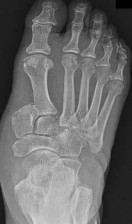

Question 24

The Lisfranc ligament is a critical stabilizing structure of the midfoot. Between which two bones does the primary interosseous Lisfranc ligament traverse?

Explanation

The Lisfranc ligament is a strong interosseous ligament that connects the lateral aspect of the medial cuneiform to the medial aspect of the base of the second metatarsal. It is critical for the stability of the tarsometatarsal joint complex, particularly because there is no transverse intermetatarsal ligament between the bases of the first and second metatarsals.